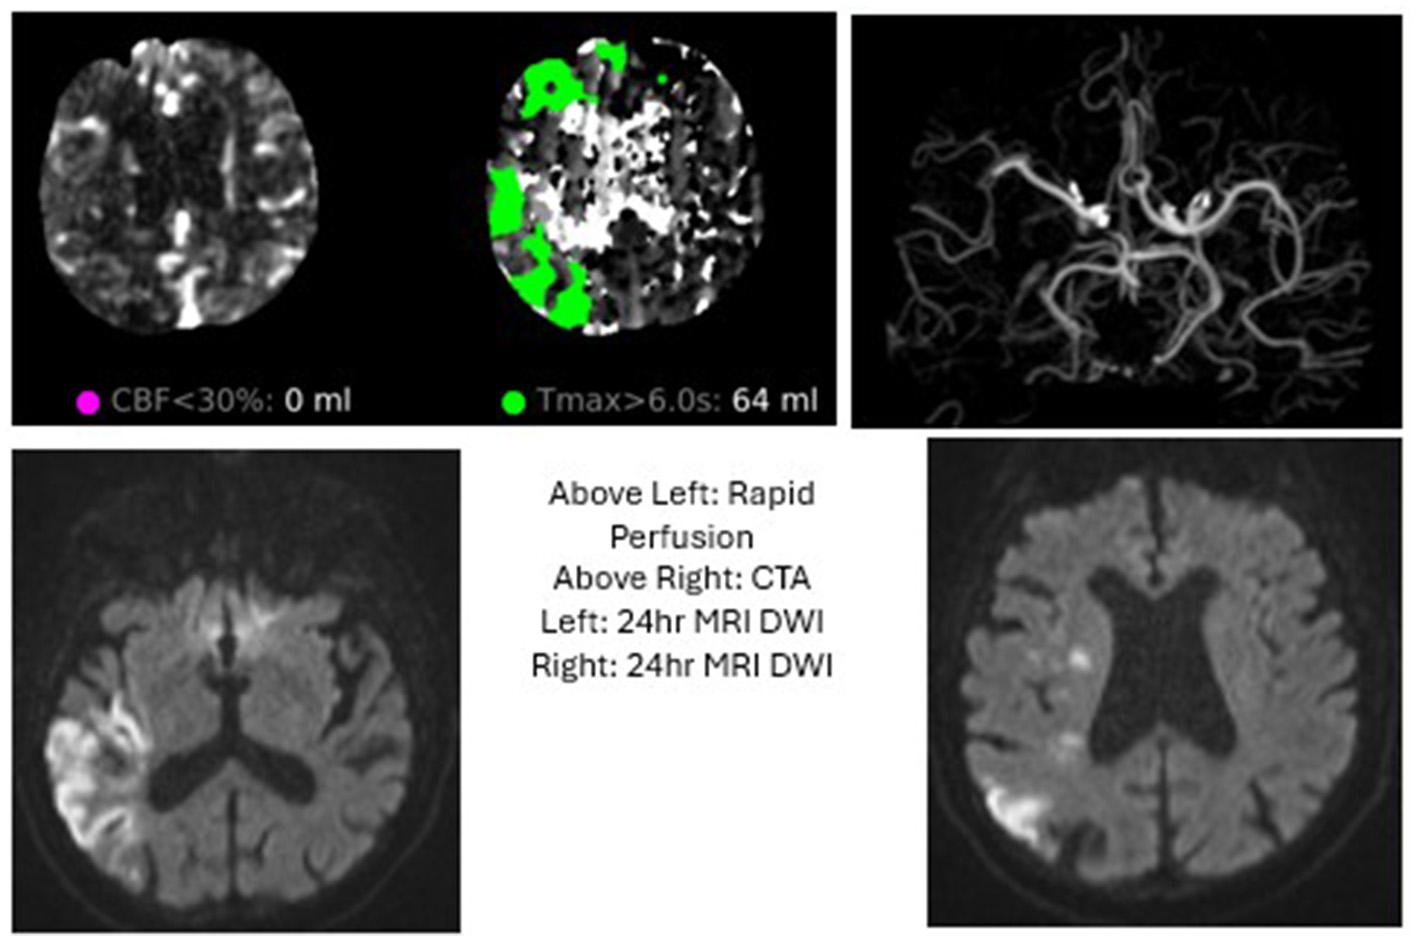

Figure 2

Case 2: The patient presented with wake up stroke and an NIHSS of 6. An MRA at that time revelaed a L M1 occlusion. A Heads Up test in IR suite was positive and MT performed with TICI2C. The patient was discharged with minimal new deficit.